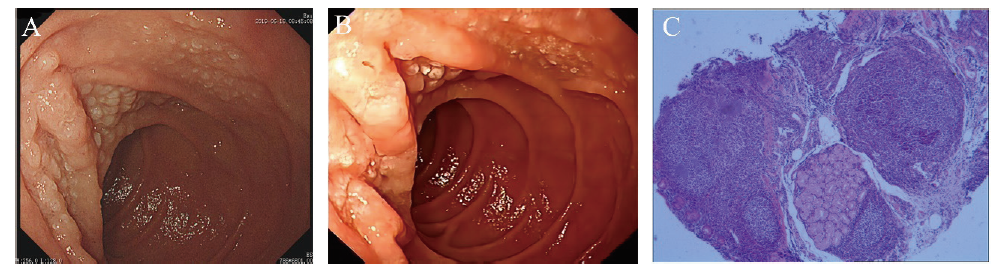

病例3 患者女,42岁,2017年12月6日因“健康体检”就诊于本院,行胃镜检查示十二指肠降部黏膜浅表性改变(图3A),当时未取活检。患者当时主诉无明显不适。2022年3月因“上腹部不适2周”于本院就诊。体格检查无殊。否认高血压、糖尿病、淋巴瘤等病史。总胆固醇>6.40 mmol/L,余实验室检查未见明显异常;胃镜示十二指肠降部见黏膜颗粒状改变(图3B),病灶处病理结果:FL(I级)(图3C);免疫组化标记结果:肿瘤细胞CD20(+),CD10(+),Bcl-2(生发中心+),Bcl-6(+),Ki-67(+,5%~15%),CD21(肿瘤性滤泡边缘+),LMO2(+),CD3(-)。结肠镜显示结肠多发息肉,病理结果示增生性息肉。右侧髂后上棘行骨髓穿刺活检,组织送检结果:流式细胞免疫表型、TCR基因重排、Ig基因重排、骨髓组织学均未见明显异常;PET/CT:全身氟代脱氧葡萄糖代谢未见异常增高;结合HE染色及免疫表型并排除系统性淋巴瘤累及十二指肠,确诊为D-FL(1级)。排除禁忌后于2022年4月起予R2方案化学治疗,具体为:“奥妥珠单抗针1 g,d1,来那度胺5 mg,d1~5”,每次奥妥珠单抗治疗后均有畏寒低热,3 d后可消退。电话随访患者至截稿日,目前化学治疗方案同前,主诉有时感上腹部不适,伴夜间盗汗,感乏力,其余无明显不适。

图3 病例3 D-FL患者胃镜及病理图片

注:A、B分别为2017年12月、2022年3月胃镜下十二指肠降部黏膜表现;C为2022年3月十二指肠降部黏膜病理(HE染色,40)。